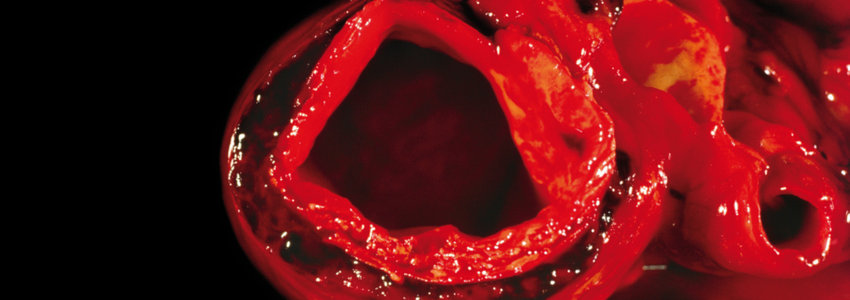

Schlanke Taille, weniger Arterienkalk

Adipositas – ermittelt über BMI, Taillenumfang oder das Verhältnis von diesem zur Körpergröße – ist ein unangefochtener Risikofaktor für…